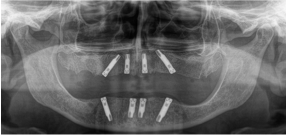

Stabilità e perfezione: il risultato di impianti posizionati con precisione e successo

© Dr.Dr. Schmitz – FreeSmile